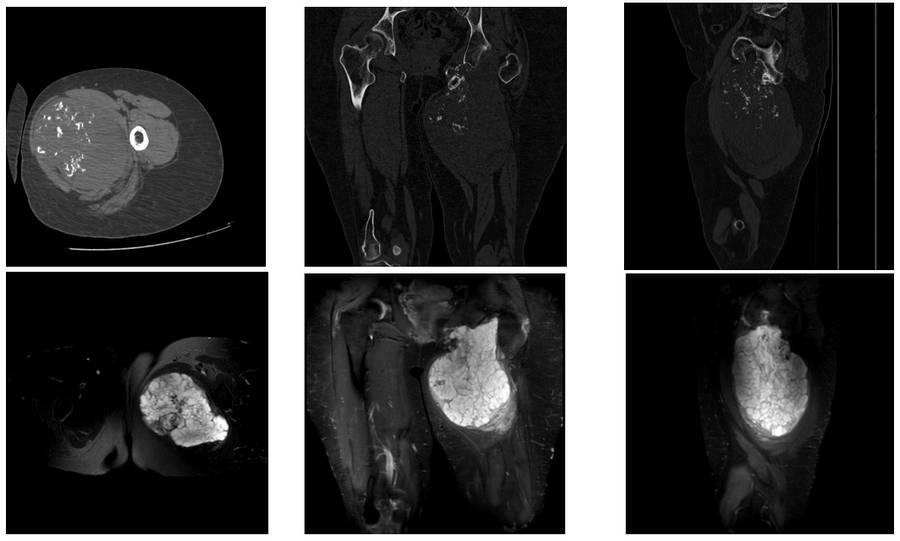

Before the surgery: CT and MRI scans show a large mass of tissue with irregularly bordered calcification originating from the pubic arm and inferior acetabulum.